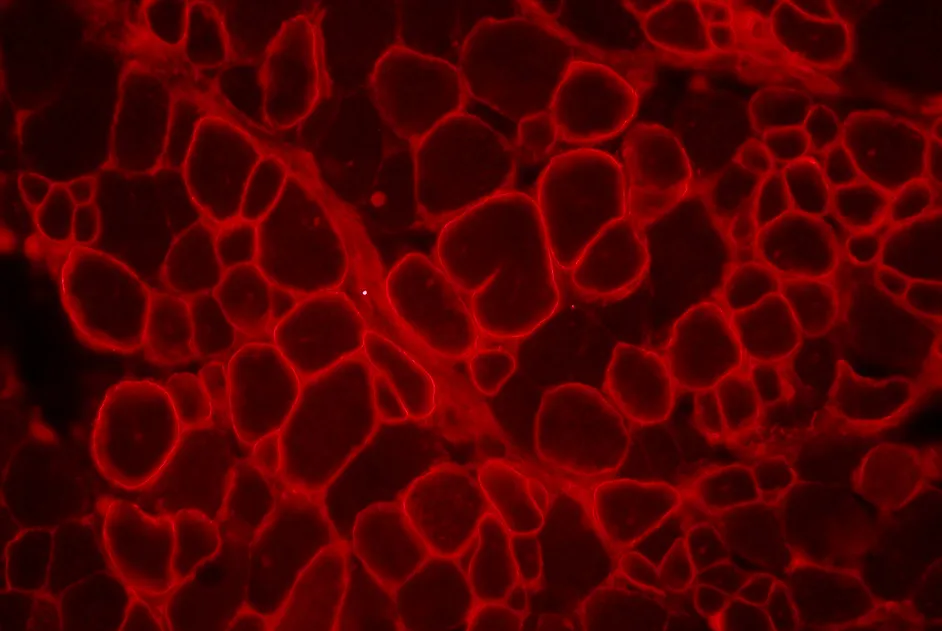

DMD : cibler le cœur en associant un peptide aux oligonuclotides

L’administration d’oligonucléotides antisens associé à un peptide cible mieux le cœur d’une souris modèle de myopathie de Duchenne.